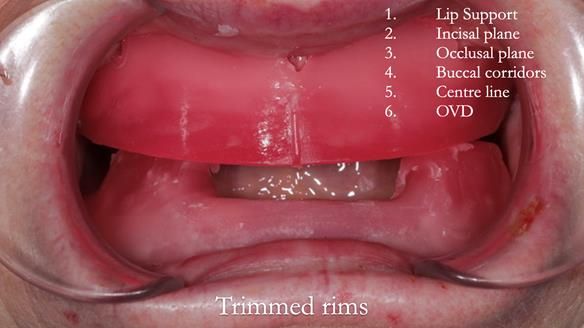

The clinical situation and treatment process is shown in detail below with photographs. 5 visits were required for the treatment. 1 review after delivery was required. I (Finlay Sutton) provided the clinical work and Rowan Garstang provided the technical work.